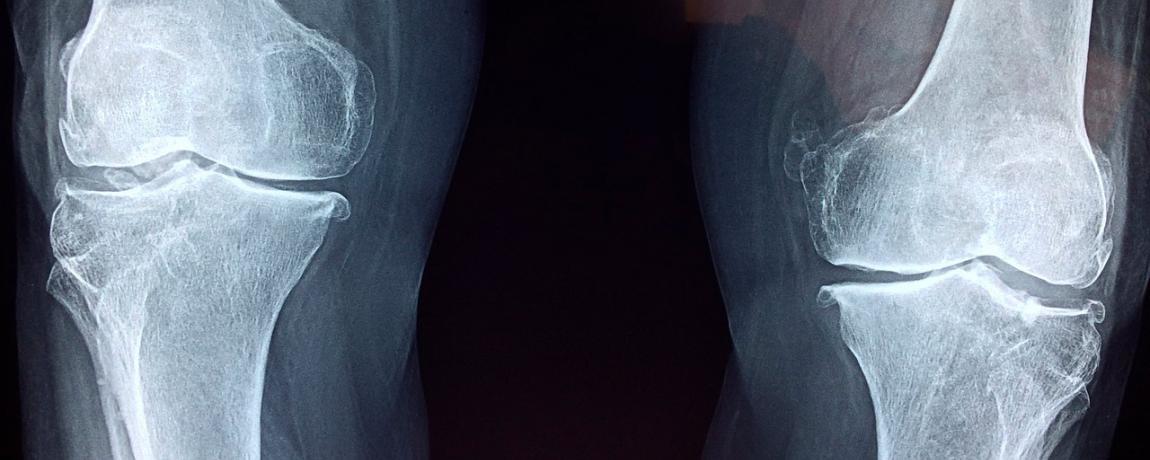

Hospital San Juan de Dios